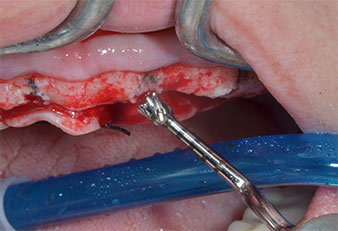

Ein flammenförmiges, diamantiertes piezochirurgisches Instrument (Piezomed I1) wurde verwendet, um die Implantatpositionen zu markieren und die Pilotpräparationen durchzuführen (Abb. 3). Dabei wurde darauf geachtet, eine Auf- und Abbewegung mit reduzierter Leistung, voller Spülung und niedrigem Druck (unter 300 g) anzuwenden. Als Nächstes wurde ein Pilotinstrument (Piezomed I2A/I2P) zur initialen Erweiterung der Implantatlager auf einen Durchmesser von 2 mm verwendet (Abb. 4), gefolgt von einem 3-mm-Instrument (Abb. 5).

Abb. 3: Die Präparation mit dem Ultraschallmarkerinstrument Piezomed I1 erfolgt mit einer Auf- und Abbewegung, parallel zur Längsachse des Arbeitsteils.

Abb. 4: Der nächste Schritt ist die initiale Erweiterung mit den Instrumenten Piezomed I2A/I2P, die in einer horizontalen Drehbewegung verwendet werden.